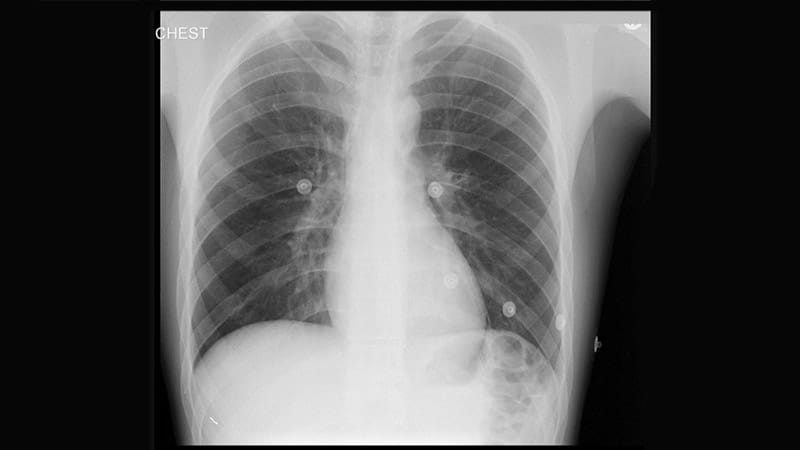

Cardiovascular Risk Reduction: Protecting the Aging Heart: More Than Risk Factors

Cardiovascular Risk Reduction: Protecting the Aging Heart: CVD Prevention in Type 2 Diabetes -